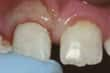

σπασμένο μπροστινό δόντι |